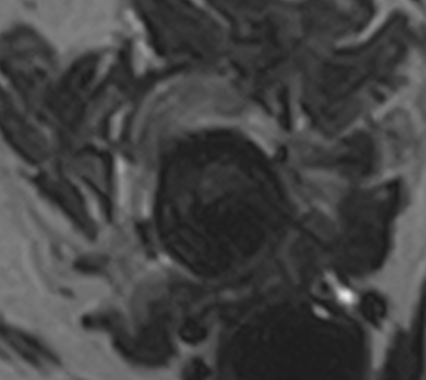

左前肢破行、後肢ふらつきを主訴に来院しました。CT・MRI撮影より、C5-6の椎間板ヘルニア、小脳背側のくも膜下嚢胞が認められました。症状が軽度から中等度、また小脳背側にくも膜下嚢胞が認められ麻酔のリスクなどを考慮し、まずは内科療法から行いました。2か月後症状の改善が認められず、症状も進行し、起立・歩行困難となりました。

左前肢破行、後肢ふらつきを主訴に来院しました。CT・MRI撮影より、C5-6の椎間板ヘルニア、小脳背側のくも膜下嚢胞が認められました。症状が軽度から中等度、また小脳背側にくも膜下嚢胞が認められ麻酔のリスクなどを考慮し、まずは内科療法から行いました。2か月後症状の改善が認められず、症状も進行し、起立・歩行困難となりました。

C5-6椎間板ヘルニア、小脳背側くも膜下嚢胞

C5-6椎間板ヘルニア、くも膜下嚢胞と診断した